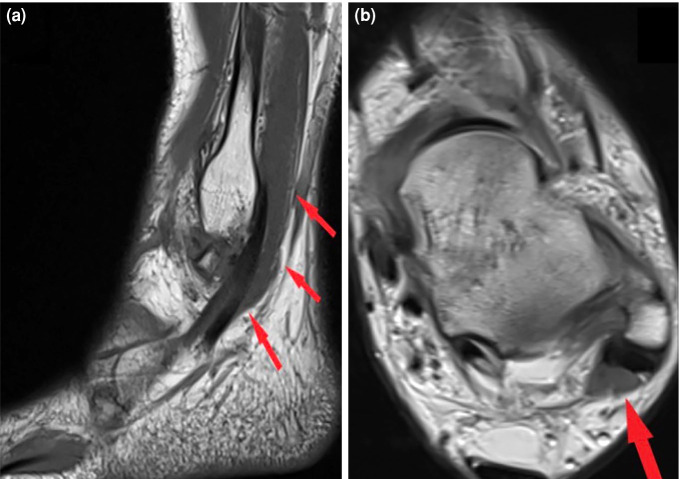

Patients and methods: Between January 2016 and December 2020, a total of 849 ankle MRIs (427 right foot, 422 left foot) in 738 patients (274 males, 464 females; mean age: 43.4±14.3 years; range, 15 to 70 years) were retrospectively analyzed. Among ankle pathologies, peroneal and flexor hallucis longus (FHL) tendinopathies were evaluated. Among the anatomical variations, retromalleolar fibular groove (RMFG) shape, os peroneum, os trigonum, peroneus quartus (PQ), flexor digitorum accessorius longus (FDAL), low-lying peroneus brevis (PB) and FHL muscles were examined. The distance of the PB and FHL musculotendinous junctions (MTJs) from designated reference points was measured. Cut-off values for PB and FHL musculotendinous junction distances were determined by receiver operating characteristic (ROC) analysis. For the reliability analysis of measurements performed by two researchers, intraclass correlation coefficient (ICC) values were calculated.

Results: Bilateral ankle MRIs of 111 patients were evaluated. The PB, PL, and FHL tenosynovitis were observed in 29.6%, 34.9%, and 38.8% of all ankles, respectively. The PB and PL tendon tears were found in 12.2% and 3.9%, respectively. A total of 47.1% of the RMFG shapes were concave, 36.7% were flat, 12.4% were convex, and 3.8% were irregular. The PQ, FDAL, os peroneum, and os trigonum were detected in 13.8%, 3.1%, 16.6%, and 20.5% of the ankles, respectively. The cut-off value of PB MTJ distance that would cause a PB tendon tear was 4.40 mm distal from reference point. The cut-off value of FHL MTJ distance that would cause FHL tendinopathy was 4.15 mm distal from reference point. The study had a statistically significantly high level of consistency between the experts (ICC=0.85).

Conclusion: The convex and irregular shapes of the RMFG, along with the anatomical variations of the os peroneum and low-lying PB muscle, constitute risk factors for peroneal tendon pathologies. The presence of the os trigonum and low-lying FHL muscle anatomical variations predispose individuals to FHL tendinopathies. The cut-off values that could lead to PB vertical tears and FHL tendinopathy were identified for the low-lying PB and FHL muscles, respectively.